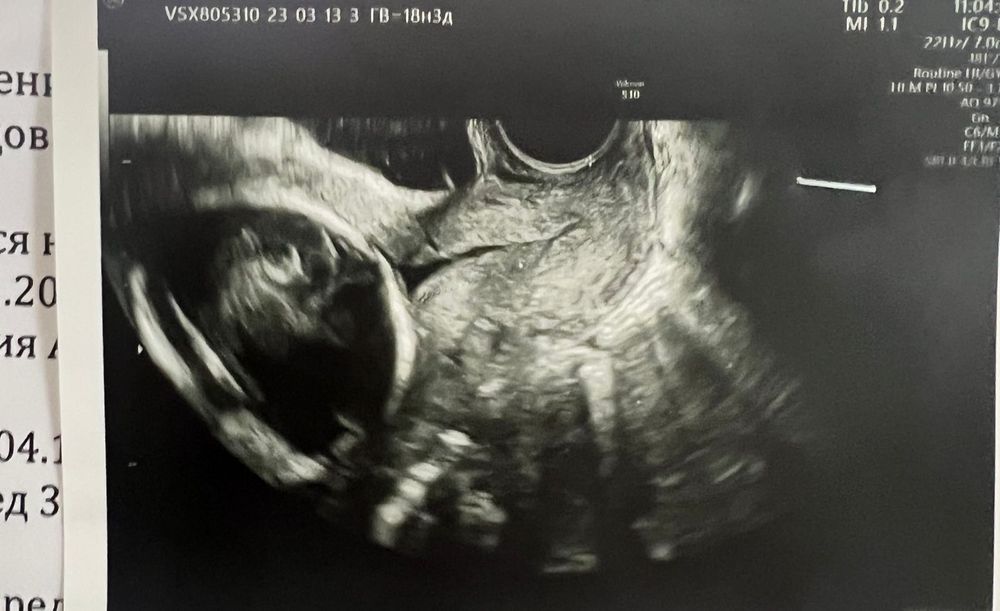

18недель 3 дня. Засветил пессарий🥺